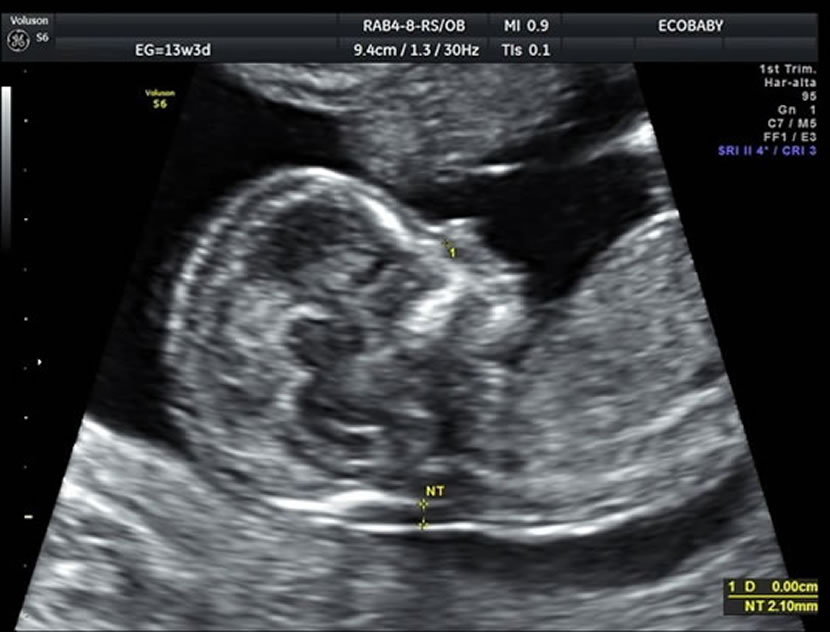

- Una ecografía entre las semanas 11-13.6 de embarazo:

> Para medir el grosor de líquido detrás de la nuca del feto (translucencia nucal)